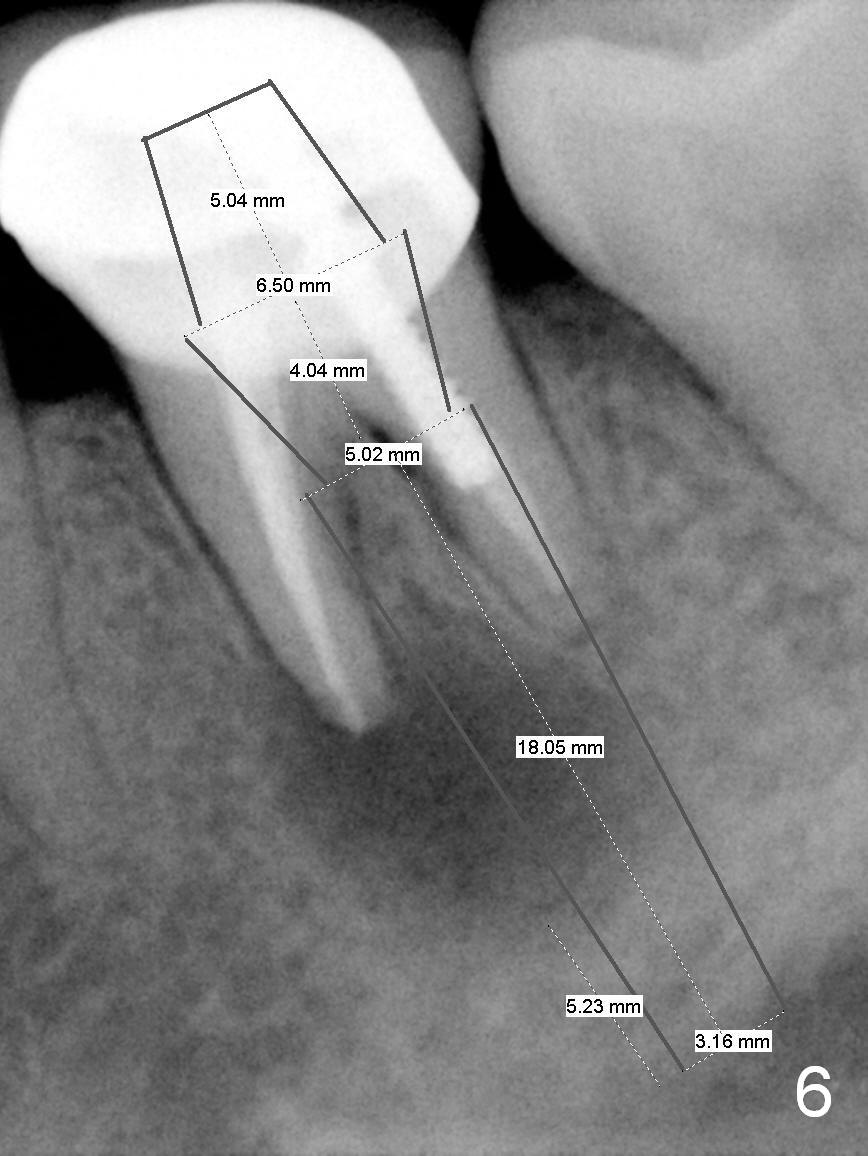

A 58-year-old lady has a long-standing periapical lesion with several episodes of acute infection (Fig.1-3, taken 10, 9 and 2 years ago, respectively). Explore the socket for size and wall integrity (Clindamycin). If the bony defect is not extensive, place a longest implant (18 mm bone-level, 20 mm tissue-level) with moderate diameter (5.5, 6 mm). Otherwise use a shorter, but wider tapered implant (7x12 mm (bone-level), 7 or 8x17 mm (tissue-level)). If the socket is extremely large, consider using 7 or 8 x20 mm cylindrical tissue-level implant. Use Bicon 2 mm pilot drill with extension to measure the socket depth and obtain 3-6 mm new bone or until 20 mm (gingival margin). Take PA. The 1st option is to use UF 3-4.7x18 mm drills at 50 RPM. Make sure that the depth is reached (septum crestal level) and check osteotomy wall integrity after each drill. Then place a 5 or 5.5x16 or 18 mm implant (Fig.6). The 2nd and 3rd options are shown in Fig.4 and 5. Due to severe infection and pain, a shorter implant is placed.